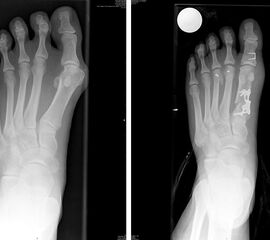

• Röntgenaufnahmen des Fußes in 2 Ebenen, a.p. stehend

Die OP Methode hat sich als Standardeingriff bei größeren Hallux valgus Fehlstellungen etabliert. Der Intermetatarsale Winkel kann sehr gut korrigiert werden. Der Erste Strahl wird stabilisiert und kann wieder Last aufnehmen. Die Verwendung einer winkelstabilen Plattenosteosynthese zur Fixation einer proximalen Osteotomie am MT 1 hat sich bereits bewährt123, insbesondere auch mit der hier verwendeten TOM Platte (Thomas M. 2009). Die V-förmige Knochenschnittführung bietet eine zusätzliche Stabilität.